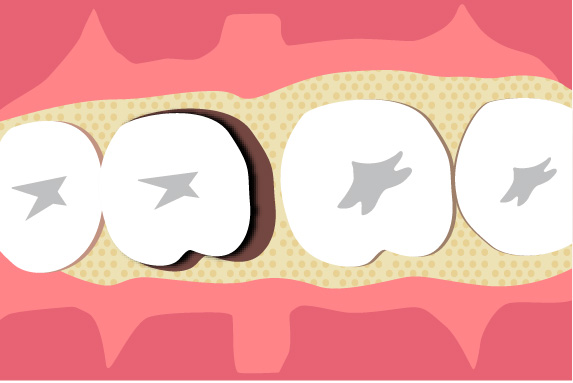

歯周組織再生療法は施術の難易度が高く、ほとんどの歯科では扱っていない内容です。

理事長の菅は日々新たな歯科治療の技術や知識を学び、それを臨床の現場に反映しています。再生療法の世界的な権威のDr. Cortellini 歯周組織再生治療のセミナーを受講。

また、トロント大学での1年間の根管治療スタディプログラムの受講や歯周再生マスターコース受講、テキサス大学ヒューストン校の歯周病コース修了、日本口腔インプラント学会専門医、AAID(アメリカのインプラントにおける最難関資格)の専門医資格を取得しております。

専門医資格を持つ医師が歯周組織再生治療を手がけるので、安心して治療を受けていただけます。